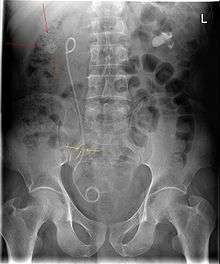

A ureteral stent, sometimes as well called ureteric stent, is a thin tube inserted into the ureter to prevent or treat obstruction of the urine flow from the kidney. The length of the stents used in adult patients varies between 24 and 30 cm. Additionally, stents come in differing diameters or gauges, to fit different size ureters. The stent is usually inserted with the aid of a cystoscope. One or both ends of the stent may be coiled to prevent it from moving out of place; this is called a JJ stent, double J stent or pig-tail stent.